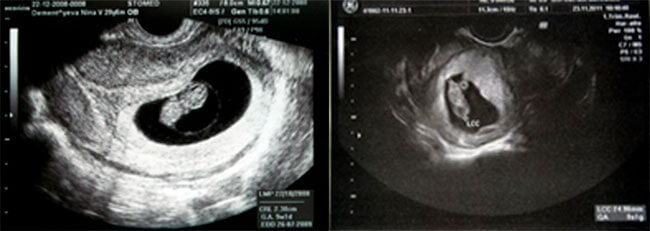

5-6 hepdelik düwünçek USB şeýle şekilde görünýär:

Ýatgyda içi embrionly tohum ýumurtgasy ösüp başlaýar. Ol ýatgynyň diwaryna berk ýapyşyp durýar. Bu döwürde embrion heniz çaga meňzemeýär, emma ene-ata hökmünde siz täze ýaşaýşa başlangyç berendigiňize begenýärsiňiz.

5-6 hepdelik embrionsyz tohum ýumurtgasy bolsa şeýle görünýär:

Bu ýagdaýa anembrioniýa diýilýär. Tohum ýumurtgasy boş. Edil towuk ýumurtga basyranda arasynda käbiriniň pak çykyşy ýaly boş. Bu duýgy bolsa ýerine düşmedik azap, myrat bolmadyk maksat ýaly ýürek gyýyjy. Foliý turşylygyny magniý, E witamini ýaly dürli derman serişdelerini ulanansyňyz. Zor bilenem bolsa, şowsuz göwreliligiň öňüni almak üçin dýufaston içensiňiz. Emma hemmesiniň netjesi – boşluk.